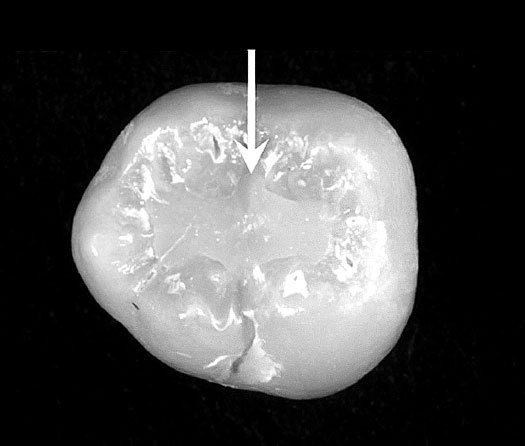

![]() ![]() Если мы посмотрим и почитаем более ранние работы Карен Харди и её коллег, изучавших питание первых гоминидов по молекулам, найденным в окаменелых зубных налетах неандертальцев возрастом около 50 000 лет из города Эль-Сидрон, в Испании, то найдем множество свидетельств того, что зоофармокогносия с гоминидами дружат достаточно давно. В одном образце от женщины с абсцессом зуба команда определила соединения, которые, вероятно, происходят из тысячелистника и ромашки, достаточно горьких растений с низкой питательной ценностью, но известных своими лечебными свойствами даже сегодня. Позже генетики исследовали зубной камень того же неандертальца на других зубах и обнаружили ДНК тополя – дерева, которое содержит салициловую кислоту, естественное обезболивающее, используемое сегодня в виде аспирина, а также разновидность Penicillium. Возможно, крохотные фрагменты ДНК этих организмов случайно оказались во рту неандертальца, пока она спала на земле, жила на природе и экспериментировала с кулинарией. Но также возможно, что эта женщина страдала от зубной боли и дентальной инфекции и намеренно принимала определенные лекарства: антибиотик на основе пенициллина, обезболивающее на основе тополя и противовоспалительное из ромашки или тысячелистника. Если бы это было так, то Нобелевская премия должна была быть отдана этой женщине на 50 000 лет раньше, чем Флемингу. Но так ли всё просто? Хотя идея самолечения растениями не является чем-то новым для палеолита, возможность активно изучать это явление и строить гипотезы появилась не так давно. Только в XXI веке мы научились восстанавливать химические биомаркеры и идентифицировать ДНК лекарственных растений. В большинстве своем помогает исследование зубного камня. Всё дело в том, что зубной камень возникает в результате кальцификации зубного налета и действует как ловушка для материалов, которые проходят через рот. Процесс образования зубного камня прекращается со смертью, именно поэтому зубной камень имеет высокую археологическую ценность. Всё, что оказалось вовлечено в его структуру и кальцифицировалось вместе с зубным камнем, было съедено при жизни и точно не попало в окаменелый рот случайно. ![]() В первом исследовании образцы зубного камня гоминида из неандертальского поселения Эль-Сидрон были идентифицированы как Achillea millefolium (тысячелистник) и Matricaria chamomilla (ромашка). Мы не можем установить, в каких количествах, как часто и с какой целью гоминид употребляла их, но мы знаем, что они действительно содержат соединения, зарегистрированные и используемые сегодня, и практически не имеют питательных свойств. Более того, если тысячелистник иногда используется для придания аромата в кулинарии, то травоядные просто-напросто его избегают из-за горького вкуса. Дальнейшие исследования привели к обнаружению Penicillium rubens, а также остатков ДНК сосны и тополя, следов употребления Coprinopsis cinerea – вида грибов, условно съедобных и также содержащих лекарственные соединения. Присутствие Penicillium rubens поднимает вопрос: а были ли известны гоминиду антибактериальные эффекты определенных форм растений/грибков в начале палеолита. Ведь, когда мы его открыли при участии Александра Флеминга в 1928 году, человечество не просто шагнуло вперед, мы уже вполне неплохо ориентировались в биологии и вовсю осваивали микробиологию. Возможно ли вообще было использовать «пенициллин» как антибактериальный агент, не зная совершенно ничего ни о его природе, ни о микрокосмосе, и не имея каких-то системных сведений? Не имея той самой науки, которая «искусство исцелять»? У нас есть лишь редкие исторические примеры такого интуитивного лечения. В арабских конюшнях раннего Средневековья седельные язвы лечили Penicillium notatum, хотя микроскопии и осознания того, как этот процесс лечения работает, не было и подавно. Есть и другие примеры, которые я приводил выше, но в описанном случае с зубным камнем речь идет про палеолит. Использование лечебных свойств требует хорошего понимания растения, потому что многие из них могут быть ядовитыми, а иногда и смертельно опасными. Например, по всей Африке насчитывается около 330 видов растений из 162 родов, использовавшихся в качестве яда при охоте и рыбной ловле. При таком разнообразии лечение неизвестного неизвестным – идея гиблая. И, если в Средние века у нас была хотя бы письменность, системность монастырских или арабских записей, то животные имеют дело с ядовитыми растениями постоянно и в совершенно разных формах. Но при этом они сохраняют здоровье, выбирают полезные, и ещё умудряются иногда использовать опасные в лечебных целях. ![]() Например, травоядные млекопитающие или избегают опасной пищи инстинктивно или обладают метаболическими механизмами расщепления / выделения токсинов. В современной науке существует гипотеза об изменении пищеварительной системы гоминидов около 1,8 миллиона лет назад, когда изменилась структура кишечника, что привело к снижению энергии, расходуемой на пищеварение, перенаправив её на деятельность мозга. Перед этим у гоминидов, возможно, был пищеварительный тракт, который включал большую заднюю кишку, или цекоколик. ЖКТ был более массивным, больше похожим на сегодняшних крупнотелых приматов, таких как пузатые гориллы. Хотя размер кишечника позволил повысить эффективность переваривания пищи, он уменьшил способность обрабатывать токсичные соединения (PSC), что привело к необходимости увеличения избирательности в выборе растений. У шимпанзе вывод токсинов может в значительной степени происходить внутри, самостоятельно, но достаточно долго или с помощью геофагии – поедания земли / глиняного субстрата. Обработка же токсинов человеком имеет тенденцию быть внешней. Возможно, именно это в конечном итоге привело к необходимости обработки и приготовления растений людьми. Но насколько эти действия на ранних этапах развития гоминидов были осознанны? Понимает ли бонобо, что он или она избавляется от глистов, понимала ли связь проблемы и её решения неандертальская женщина? Если у муравьев мы не можем даже представить какой-то личный опыт самолечения, а только лишь рассматриваем врожденный инстинкт, способный спасать их популяцию, то применимо ли к шимпанзе понятие самолечения как таковое? Или это как поедание домашним котиком травки – любопытный эволюционный факт, назначение которого выяснить чрезвычайно сложно. Или как в случае с дельфинами и фугу, это не имеет никакого отношения к медицине – дельфины, по одной из теорий, испытывают так острые ощущения. Так может, и пенициллин в зубном камне у гоминида использовали для вкуса или по какой-то прихоти? Борьба с паразитами путем изменения диеты с включением растений с определенными лекарственными соединениями широко практикуется среди разных животных – от шимпанзе и до насекомых. Но наиболее изученные примеры самолечения действительно связаны с шимпанзе (Pan troglodytes) и гориллами (Gorilla). Но идентификация действия по употреблению растений, как преднамеренного, крайне сложна, так как границы между едой и лекарствами могут быть сильно размыты. Случайное употребление, употребление ради вкуса, ритуальное – это может быть что угодно. |